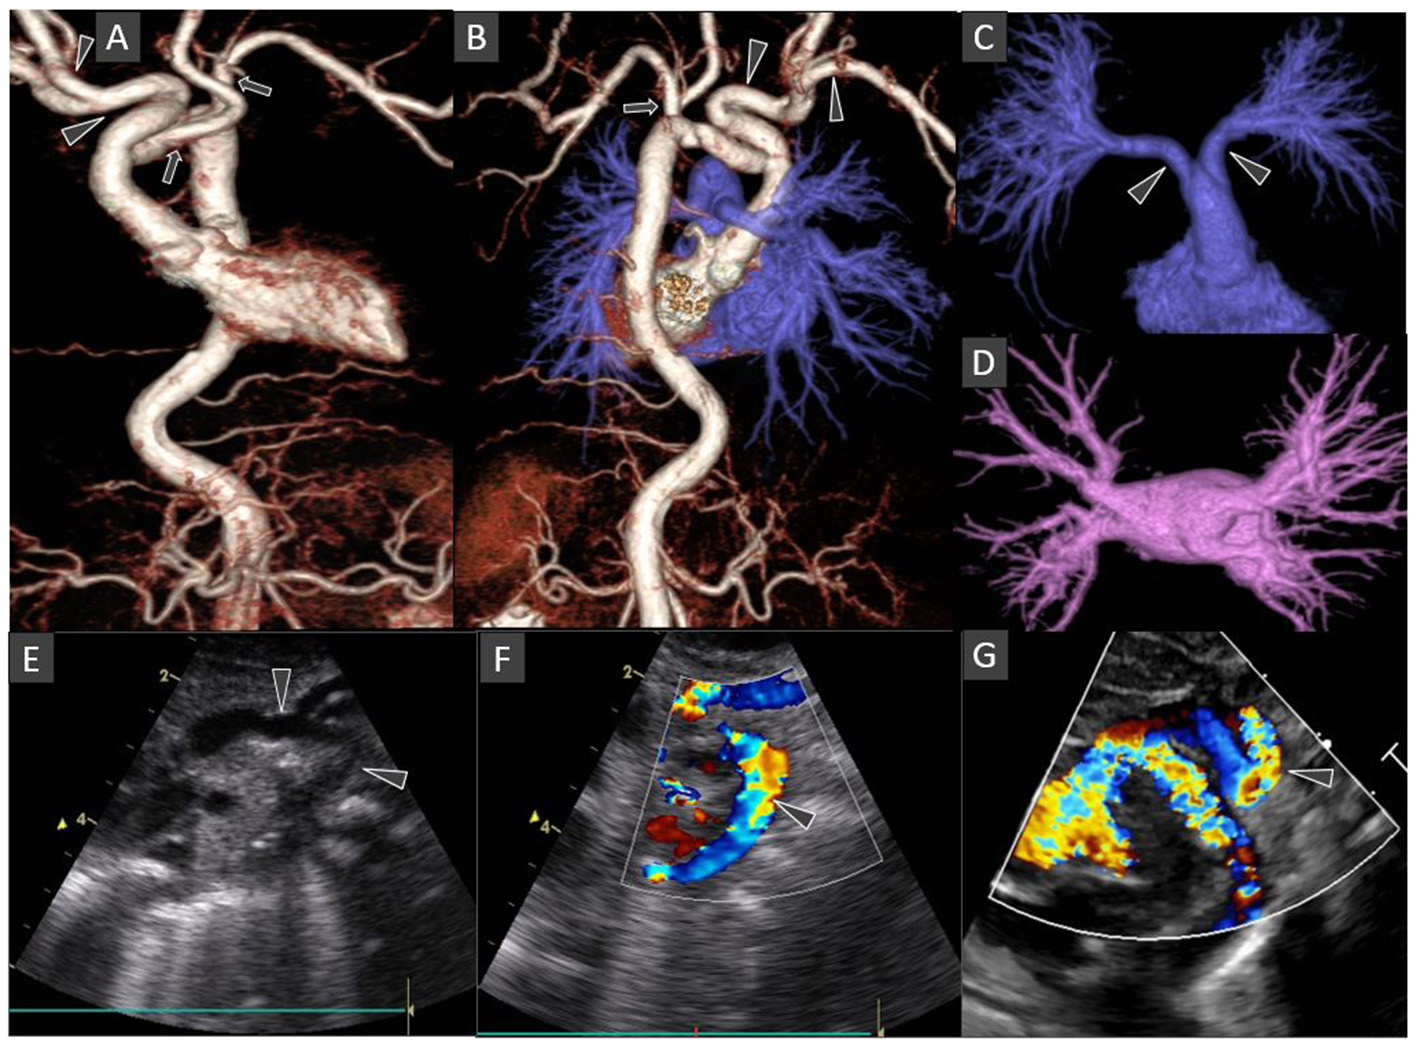

Figure 2

Chest CT Angiography 3D surface shaded display images: Anterior view of the thoraco-abdominal aorta (A); Posterior view of the combined thoraco-abdominal aorta and pulmonary arteries (B); Antero-superior view of the subtracted pulmonary arterial circulation and right atrium (C); Superior view of the subtracted pulmonary venous circulation and left atrium (D). Oblique coronal gray-scale (E); and color Doppler (F,G) echocardiography images of the aortic arch and its major branches. The left-sided aortic arch has an unusual configuration with the dilated innominate artery forming a hairpin turn before its bifurcation into right subclavian and common carotid arteries (arrowheads in A,B). The left common carotid and subclavian arteries arise from the hypoplastic mid arch (arrows in A,B). The thoraco-abdominal aorta is tortuous. Included abdominal aorta shows dilated and tortuous branches of the coeliac axis. The main pulmonary artery is short with early bifurcation with long tubular configuration and parallel proximal course of the right and left main pulmonary arteries (arrowheads in C). Normal morphology of bilateral pulmonary veins draining into the left atrium (D). Some of these findings are also demonstrated on echocardiography images (arrows in E–G).

Echocardiography showed no intracardiac abnormalities but raised suspicion of double aortic arch. The superior “arch” coursed leftward, with the right common carotid and subclavian arteries arising from it, while the hypoplastic arch coursed inferiorly giving rise to the left common carotid and subclavian arteries (Figures 2E–G). The maximum velocity across the descending aorta was estimated at 4.59 m/s (pressure gradient 99.9 mmHg). However, the neonate had normal cardiovascular examination with no differential pulse or blood pressure between upper and lower extremities.

The umbilical artery catheter (UAC) (Figure 1) was incidentally noted to have a tortuous course on radiograph on D5 of life (Figure 2A). A Computed Tomography Aortogram (CTA) was performed to evaluate the aortic arch anatomy. CTA confirmed the findings of a left-sided aortic arch with a dilated and tortuous right brachiocephalic artery forming a hairpin loop before bifurcating into the right subclavian and common carotid arteries (Figures 2B,C). The left common carotid and subclavian arteries arose from the hypoplastic transverse arch. The thoraco-abdominal aorta, and branches of the coeliac axis, appeared dilated and tortuous corresponding with the tortuous course of UAC. The branch pulmonary arteries appeared unusual as well, with proximal segments coursing parallel to each other before branching to the left and right, respectively (Figures 2A–C). The pulmonary veins were normal (Figure 2D). The abdominal aorta and the celiac axis branches were dilated and showed tortuosity. The UVC was also tortuous as evidenced in the abdominal roentgenogram.